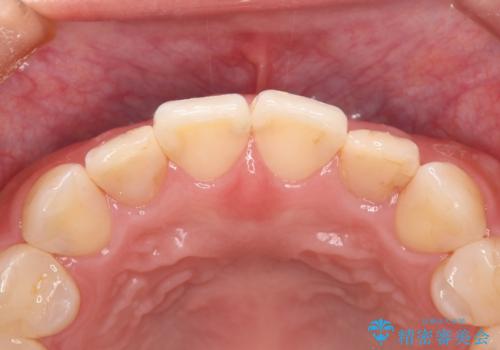

- 食べ物が歯間にはさまることを主訴に来院された患者様です。レントゲンより上顎両側切歯に根管治療が実施されていますが、被せ物が入っておらず、充填物に劣化像もみられました。歯の色の差も気にされていたのでオールセラミッククラウンにて治療いたしました。

より歯の色をきれいに見せたいという希望があったため、ホワイトニングも実施いたしました。食べ物の詰まりも改善し、きれいな仕上がりになったので非常に満足いただけました。